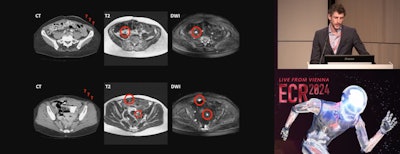

In his talk, Max Lahaye, MD, PhD, from the Netherlands Cancer Institute in Amsterdam discussed his team's findings which showed that DW-MRI could perform a complete primary and interval debulking with high accuracy.

Max Lahaye, MD, of the Netherlands Cancer Institute in Amsterdam presents findings on the clinical impact of dedicated MR staging of ovarian cancer patients during ECR 2024.

The Netherlands Cancer Institute, Leiden University Medical Center, and Catharina Ziekenhuis Teaching Hospital are collaborating on the multicenter MISSION trial. Part of the trial's overarching work includes predicting whether complete debulking surgery could be achieved and whether or not DW-MRI could be a cost-effective method in the diagnostic work-up of advanced ovarian cancer.

The researchers designed their prospective study to follow a routine care path. The study also evaluated surgical outcomes, interobserver agreement, and whether MRI could depict small lesions not detected during the initial surgical inspection.

The study included 220 advanced-stage (FIGO III/IV) ovarian cancer patients ages 65 to 67 who were scheduled for primary (n = 27) or interval (n = 193) debulking between 2018 and 2023. Anyone with contraindications for debulking or MRI, and no prior malignancy up to five years before surgery, was excluded.

Lahaye added that surgeons were not informed about the preoperative MRI and did not have an opportunity to see the MRI results until after they had inspected the whole abdomen and evaluated a PCI score.

In addition, after seeing the DW-MRI imaging data, surgeons confirmed MRI findings that they missed in their initial surgical inspection. Finally, the team concluded that MRI appeared to be budget-neutral as a result of ruling out diagnostic laparoscopy in some cases.